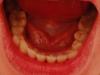

Елена. Опубликовано 12 февраля, 2009 Поделиться Опубликовано 12 февраля, 2009 Помогите определить дальнейший план лечения?Изначально было небольшое искривление. Верхние клыки выпирали вперед. Верхние 1-ки начинали находить друг на друга. Нижняя лева четверка была развернута. Носила брекет-систему 9 месяцев. Все зубы встали на место. ТОлько нижняя 4-ка слегка оставалась повернутой и нижние 7-ки и 8-ки выходили немного выходили из ряда зубов. Нижняя 4-ка отставала от верхнего ряда зубов. Ортодонты сказали, что все ровно и лучше не будет. Можно снимать. Подрезали еще уздечку и надели ретейнер на н.ч. и в.ч. Через 4-5 месяцев нижняя 4-ка начала опять разворачиваться. Брекеты одели снова. Носила еще около 6 месяцев. Зуб встал на место, но все равно не до конца. Сняли. Через полгода все повторилось. Носила каппы. Нижние 1,2,3-ки пошли в сторону. Сейчас мне кажется начал меняться прикус. При ссмыкании зубов челюсть немного в сторону ходит. Врач предлагает удалять 8-ки. Консультировалась с другим врачом - посоветовал 4-ки.ПРо удаление 8-к никогда не слышала. Подскажите, что делать Ссылка на комментарий

Премоляр Опубликовано 12 февраля, 2009 Поделиться Опубликовано 12 февраля, 2009 (изменено) Елена, рецидив происходит из-за неправильно проведенного лечения(или расфиксирования ретейнера). Жаль что нельзя посмотреть изначальную ситуацию в полости рта.Но предварительные выводы уже вырисовываются-если вам уже 2(!!!) раза ставили брекеты и это не привело к стабильному результату-это говорит о неправильно выбранном плане лечения или неправильной механике лечения.Вопрос о удалении невозможно решить в условиях форума.(удаление 8рок проводится с целью предотвращения избыточного давления на зубной ряд во время их прорезывания с целью предотвращения рецидива)Есть хирург.методы предотвращения нежелательной ротации отдельных зубов-например иссечение круговой связки(тканей пародонта) и т.д...Ваш врач должен был сделать выводы еще после первого рецидива.По фото видно что врач не откорректировал соотношение зубов с антагонистами(верхние с нижними слева),виден промежуток...Не создал плотные контакты...Возможно из-за этого верхняя 4 ка "разворачивает" нижнюю,попадая при накусывании не в фиссуру,а в бугор(написал максимально понятно для вас) Что тут посоветуешь??? Искать грамотного специалиста...Ну и "бог любит троицу" Изменено 12 февраля, 2009 пользователем Премоляр Ссылка на комментарий